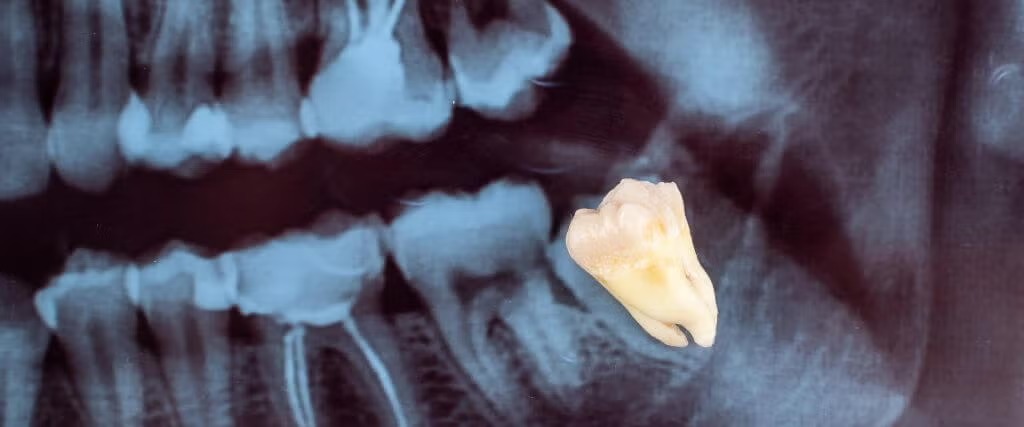

When it comes to oral surgery, few procedures are more common than removing wisdom teeth. While they can help with chewing when they come in